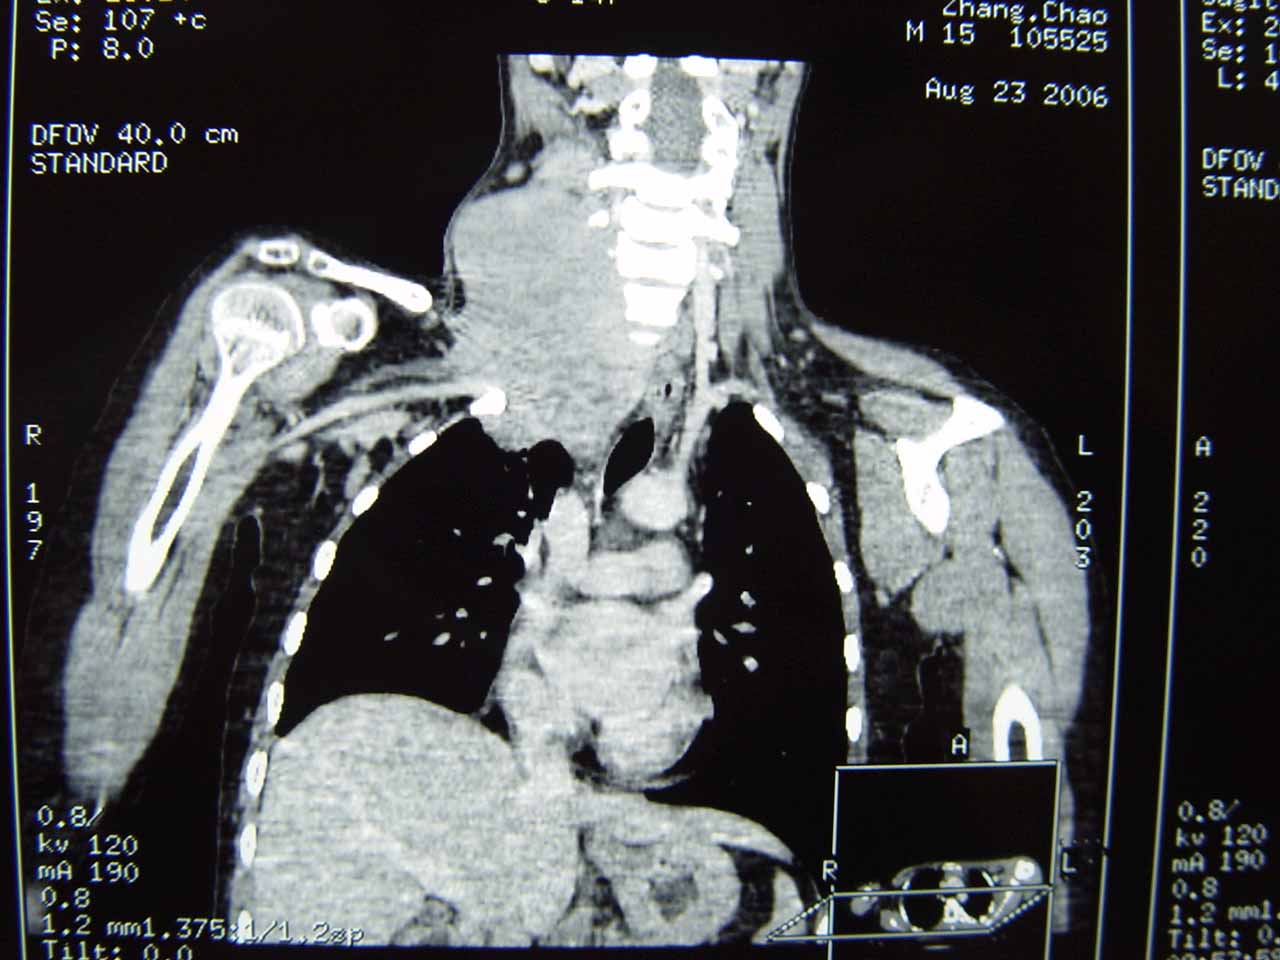

近日,我科张艳主任收治了一名年仅15岁的巨型神经纤维瘤患者。患儿入院时右颈部可见一婴儿头部大小的肿瘤,经检查发现该肿物上界位于颅底,下界已深入胸腔,并已经侵犯周围诸多重要的血管及神经。由于神经纤维瘤属于潜在恶性肿瘤,同时考虑到患儿年龄较小,家属救子心切,因此虽然该患儿病情危重,手术难度极高,张艳主任还是在第一时间决定对患儿进行手术治疗。因为该肿瘤涉及人体多个重要器官,除切除颈部肿物还要切断锁骨切除胸腔内的肿物,所以手术最终在头颈2科张艳主任、高明主任、肺部肿瘤科王长利主任及头颈2科各医生的共同努力下成功完成。手术过程非常顺利,张艳主任成功将罕见的巨型肿瘤切除,同时为患儿保留了生活必需的生理功能。这次手术不但成功挽救了患儿的生命,同时充分体现了我科的团队合作及人道主义精神。术后患儿恢复顺利,一切安好。